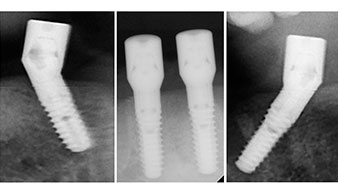

Направи се скенер с триизмерна компютърна томография (CBCT, Planmeca), за да се подпомогне планирането и да се намалят рисковете. Той показа, че качеството и количеството на наличната кост са достатъчни за операцията и имедиатното възстановяване, използвайки Fast & Fixed метод. Следвайки протокола за тази концепция, имплантите са поставени на 35, 32, 42 и 45 позиция. Ангулирането на дисталните импланти до 45° промени профила в задната зона и осигури по-голяма поддръжка в многоъгълната зона (Фиг. 3).

Това кореспондира със следващата зададена програма на Implantmed. Тук виждаме обратния наконечник на W&H под наклон от 45° ъгъл мезиокаодално в областта на 45, с цел да се предпази менталният нерв. Изходът на менталния нерв е използван като анатомична препратка за всички пробивания в тази зона. Следващите отвори са пробити при намалени обороти от 300 rpm (Фиг. 10 и 11).

Ангулираните абатмънти (35°) са завити в имплантите, за да компенсират отклонението от дисталните импланти, така че в резултат профилът на разположение на всички импланти да е възможно най-перпендикулярен на нивото на захапката. Това е предпоставка за оклузално поставяне на временна и впоследствие на постоянна протеза (Фиг. 15 и 16).

Светлината увеличава контраста в оралната кухина и подобрява визуалното възприятие. Обратният наконечник и S-11 прав наконечник на W&H са с външно охлаждане, което е голямо предимство по отношение на физиологичния разтвор, който достига точно, където трябва и може да бъде впоследствие редуциран, ако е необходимо. Правите и обратни наконечници могат да бъдат разглобени, което е силно препоръчително от гледна точка на хигиената и стерилизацията. Поставени са четири импланта SKY с размери 4.0 x 14 мм.